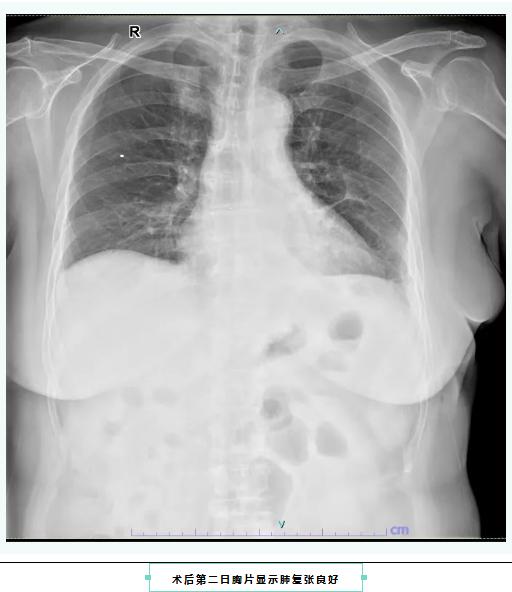

术后第二日胸片显示肺复张良好

胸外科主任马胡赛表示:“肺段切除仅切除病变所在的解剖性肺段,而非整个肺叶,因此能保留更多的健康肺组织。特别适合早期肺癌(肿瘤直径≤2cm、无转移)、磨玻璃结节(GGO)、原位腺癌或微浸润腺癌患者。JCOG0802等国际临床试验表明,在肿瘤≤2cm且实性成分比例适中时,肺段切除在局部控制和长期生存上不劣于肺叶切除。随着影像技术的发展,越来越多的早期肺癌在体检中被发现,微创解剖性肺段切除已成为治疗早期非小细胞肺癌的重要选择。”术后,患者在护理团队的精心照护下恢复迅速,术后第一天即下床活动,第二天拔除胸腔引流管,一周后顺利出院。随访至今,患者无任何并发症发生。